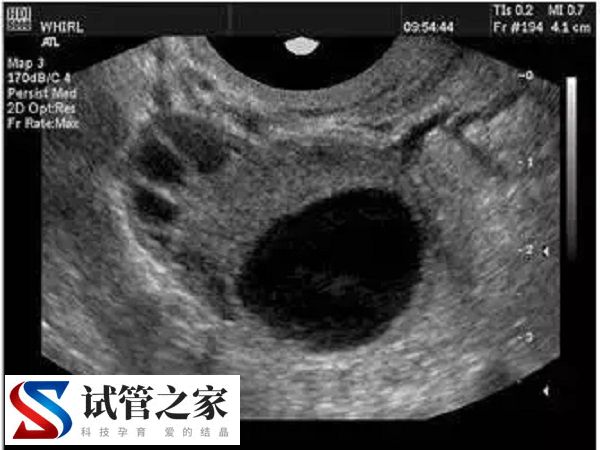

医院开展第三代试管婴儿技术多年,成功率高,服务质量好,深受患者信赖。该院的试管婴儿中心位于医院的生殖医学中心,拥有独立的实验室和手术室,并配备了先进的设备,如显微操作系统、冷冻系统、胚胎培养系统等。